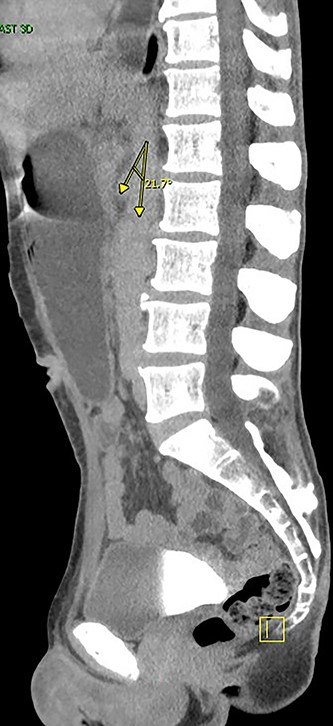

Two days later, the patient returned with emesis and poor oral intake. A repeat CT scan of the abdomen and pelvis with IV contrast was notable for increased fluid distention of the stomach and proximal duodenum with an abrupt transition at the level of the narrowed aortomesenteric interval. The aortomesenteric distance measured 5 mm with an SMA angle of 21 deg, confirming SMA syndrome (Figs 1 and 2). He was admitted, started on total parenteral nutrition (TPN). Preoperative endoscopy was performed revealing an area of constriction in the third part of duodenum. The duodenum was dilated without lesions or strictures; however, the endoscope could not traverse this area.

Angle between superior mesenteric and aorta artery measuring 21. deg.